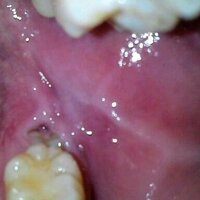

頬の内側 奥歯のすぐ上が痛いです 注意 口腔内写メあります 写メ Yahoo 知恵袋